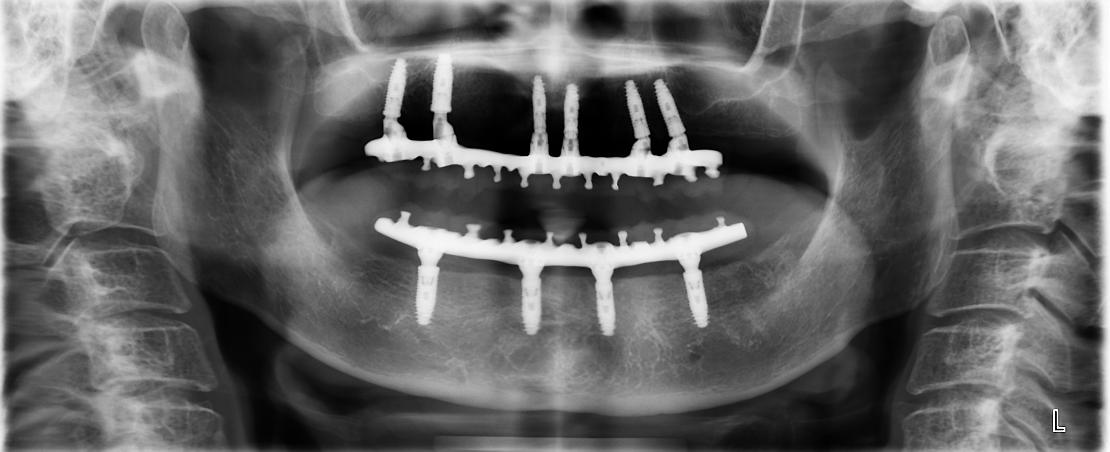

All-on-Fou/Six

近年來由於人工植牙的技術普及,患者大都知道植牙可做固定式假牙,但同樣的有時患者因為身體、經劑因素等受限,也可以考慮植入幾支人工植牙,再完成固定可撤式活動義齒,這樣可讓活動式假牙的固定性有效加強。通常上顎可用6支植體,下顎則4-5支植體固定,如需更穩定的受力,亦可再增加植體數目。(圖52-55)

圖52

圖53

圖54

圖55

參考病例: 固定式植牙牙橋&固定可撤式活動義齒